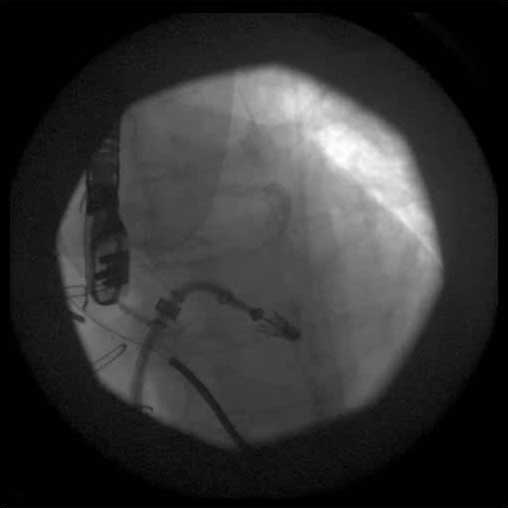

4. From the right femoral venous puncture, a TEE guided trans-septal puncture of the septum is performed using a standard transseptal kit (Figure 7) with the Brockenbrough needle, a dilator and a Mullins sheath. The site of the puncture is decided using a standardized approach which optimizes the maneuverability of the delivery system. The puncture is usually high and posterior in the fossa ovalis. After successful septal puncture, the Mullins sheath is parked in the left atrium and the patient is heparinized to achieve an ACT of at least 250 seconds.